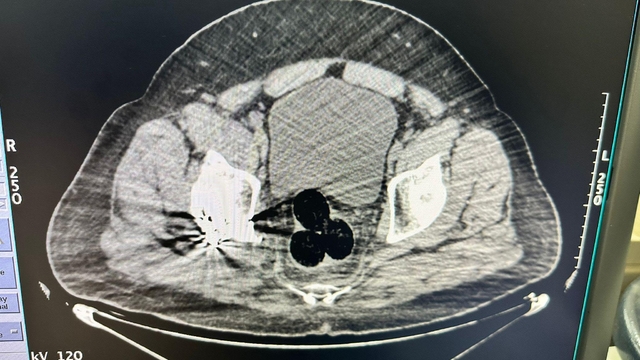

IĞDIR'da, İran'dan yurda giren kişinin hastanede yapılan radyolojik görüntülemede İran uyruklu şüphelinin makatında uyuşturucu tespit edildi. Şüpheli ile onunla bağlantılı olduğu tespit edilen 2 kişi tutuklandı.

Iğdır Emniyet Müdürlüğü Narkotik Suçlarla Mücadele Şube Müdürlüğü ekipleri tarafından, İran'dan ülkeye giren bir kişi, şüphe üzerine hastaneye götürüldü. Burada yapılan radyolojik görüntülemede şüphelinin makatında 3 parça halinde yabancı cisim tespit edildi. Hastanedeki operasyonla çıkarılan 3 pakette 130 gram metamfetamin ele geçirildi. Şüpheli gözaltına alınırken, soruşturma kapsamında polis, bu kişiyle bağlantılı olduğu ve aldıkları uyuşturucuyu kentte kullanıcılara sattığı tespit edilen 2 şüpheliyi daha yakaladı. 47 gram daha metamfetamin ele geçirildi.